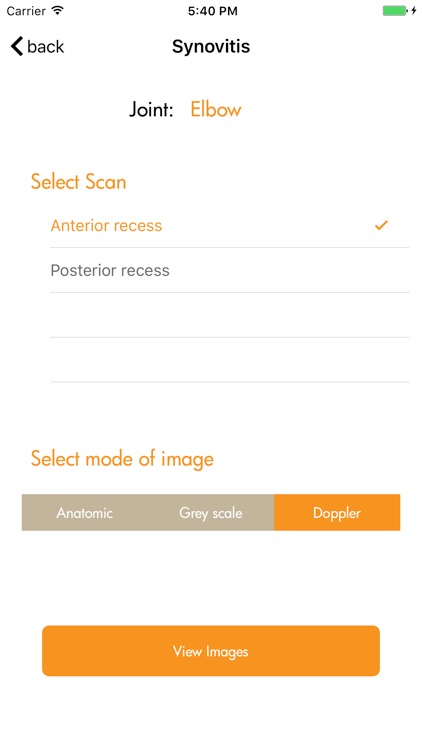

Ultrasound detected synovitis is a powerful imaging tool used worldwide that helps diagnose, monitor and treat patients with rheumatoid arthritis . RAUSSA application has been developed to help you score joint and tendon ultrasound grey scale and Doppler detected synovitis while performing your ultrasound examination. RAUSSA is made-up of almost 400 images from patients with rheumatoid arthritis. Takes no more than 2 minutes to learn! In every area you can look at a representative anatomic specimen image, up to 4 different US images with the same grey scale or Doppler mode score. , Dr. J. Uson MD PhD , Dr. I. Möller MD PhD and Dr. E. Naredo MD PhD, experts in rheumatologic ultrasound have obtained the images in this app.

Ultrasound detected synovitis is a powerful imaging tool used worldwide that helps diagnose, monitor and treat patients with rheumatoid arthritis . RAUSSA application has been developed to help you score joint and tendon ultrasound grey scale and Doppler detected synovitis while performing your ultrasound examination. RAUSSA is made-up of almost 400 images from patients with rheumatoid arthritis. Takes no more than 2 minutes to learn! In every area you can look at a representative anatomic specimen image, up to 4 different US images with the same grey scale or Doppler mode score. , Dr. J. Uson MD PhD , Dr. I. Möller MD PhD and Dr. E. Naredo MD PhD, experts in rheumatologic ultrasound have obtained the images in this app.

The ultrasound definitions and semi-quantitative scoring method used in this app. are those driven and reported by OMERACT (Outcome Measures in Rheumatology in Clinical Trials) validated for diagnoses and monitoring inflammatory activity in patients with rheumatoid arthritis (Bruyn GA, Naredo E, Iagnocco A. J Rheumatol 2015;42 (11):2172-6).